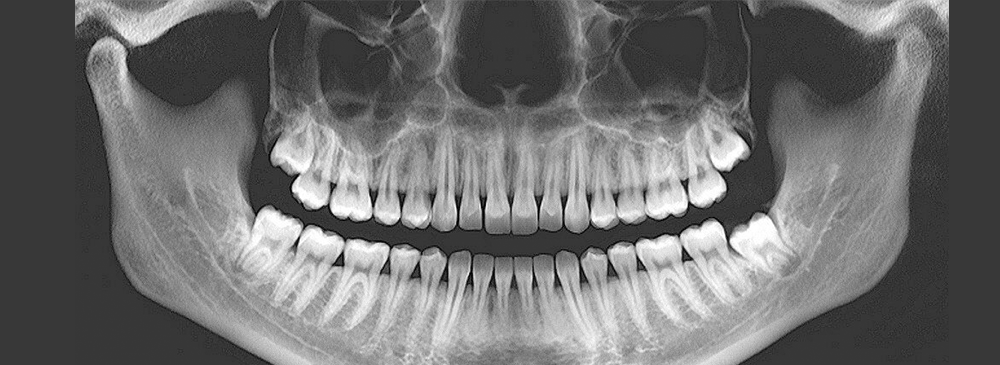

An OPG is a specialised panoramic X-ray that captures the entire mouth in one image — from the upper and lower jaw to all your teeth and the surrounding bone structure. This allows dental professionals to detect problems that may not be visible during a regular dental check-up. At our Pallavaram centre, we combine advanced digital OPG technology with experienced radiology staff to ensure each scan is clear, precise, and safe for patients of all ages. Our goal is to make dental diagnosis faster, more comfortable, and more reliable, so you can get the right treatment without unnecessary delays.

An Orthopantogram is essentially a panoramic dental X-ray that gives a “big picture” view of your oral health. Unlike small, targeted dental X-rays that focus on a single tooth or a small section of the jaw, the OPG provides a complete visual map of the mouth. This includes the jaw joints, nasal area, sinuses, and the relationship between teeth and jawbones. Dentists rely on OPGs to see issues that could remain hidden without such an extensive view.

An OPG, or orthopantomogram, is a special type of dental X-ray that captures a panoramic view of your entire mouth in a single image. Unlike small intraoral X-rays, this scan shows all teeth, both upper and lower jaws, jaw joints, and surrounding bone structures in one shot. Dentists recommend OPGs for detecting impacted wisdom teeth, jaw fractures, infections, cysts, and even early signs of oral cancer. Because it gives a complete picture, it’s a key part of pre-treatment planning for braces, implants, and oral surgeries.